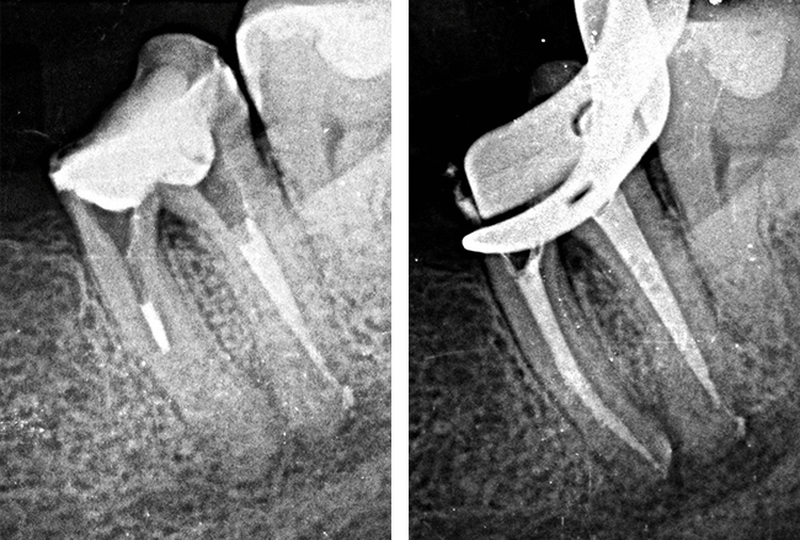

Powtórne leczenie endodontyczne jest najczęściej wynikiem rozwoju patologicznych zmian w obrębie korzenia zęba powstałych w wyniku nieprawidłowego leczenia pierwotnego.

Leczenie re-endo polega na usunięciu materiału, którym był wypełniony kanał, zlokalizowaniu zaistniałej nieprawidłowości, oczyszczeniu oraz ponownym wypełnieniu. W trakcie powtórnego leczenia kanałowego często występuje konieczność ominięcia wytworzonego w kanale stopnia, usunięcia starego wypełnienia lub złamanego narzędzia z kanału.

Potrafimy w sposób bezpieczny dla zęba usunąć różnego rodzaju wkłady koronowo – korzeniowe (tzw. sztyfty).

Pomaga w odnalezieniu wszystkich kanałów, w usuwaniu złamanych narzędzi oraz leczeniu kanałów zobliterowanych (zarośniętych) o trudnej anatomii.

W każdym naszym gabinecie znajduje się aparat RVG. Zdjęcia rentgenowskie są nieodłącznym elementem leczenia endodontycznego, dzięki nim lekarz jest w stanie sprawdzić dokładną budowę korzeni oraz skontrolować stan po zakończonym zabiegu.